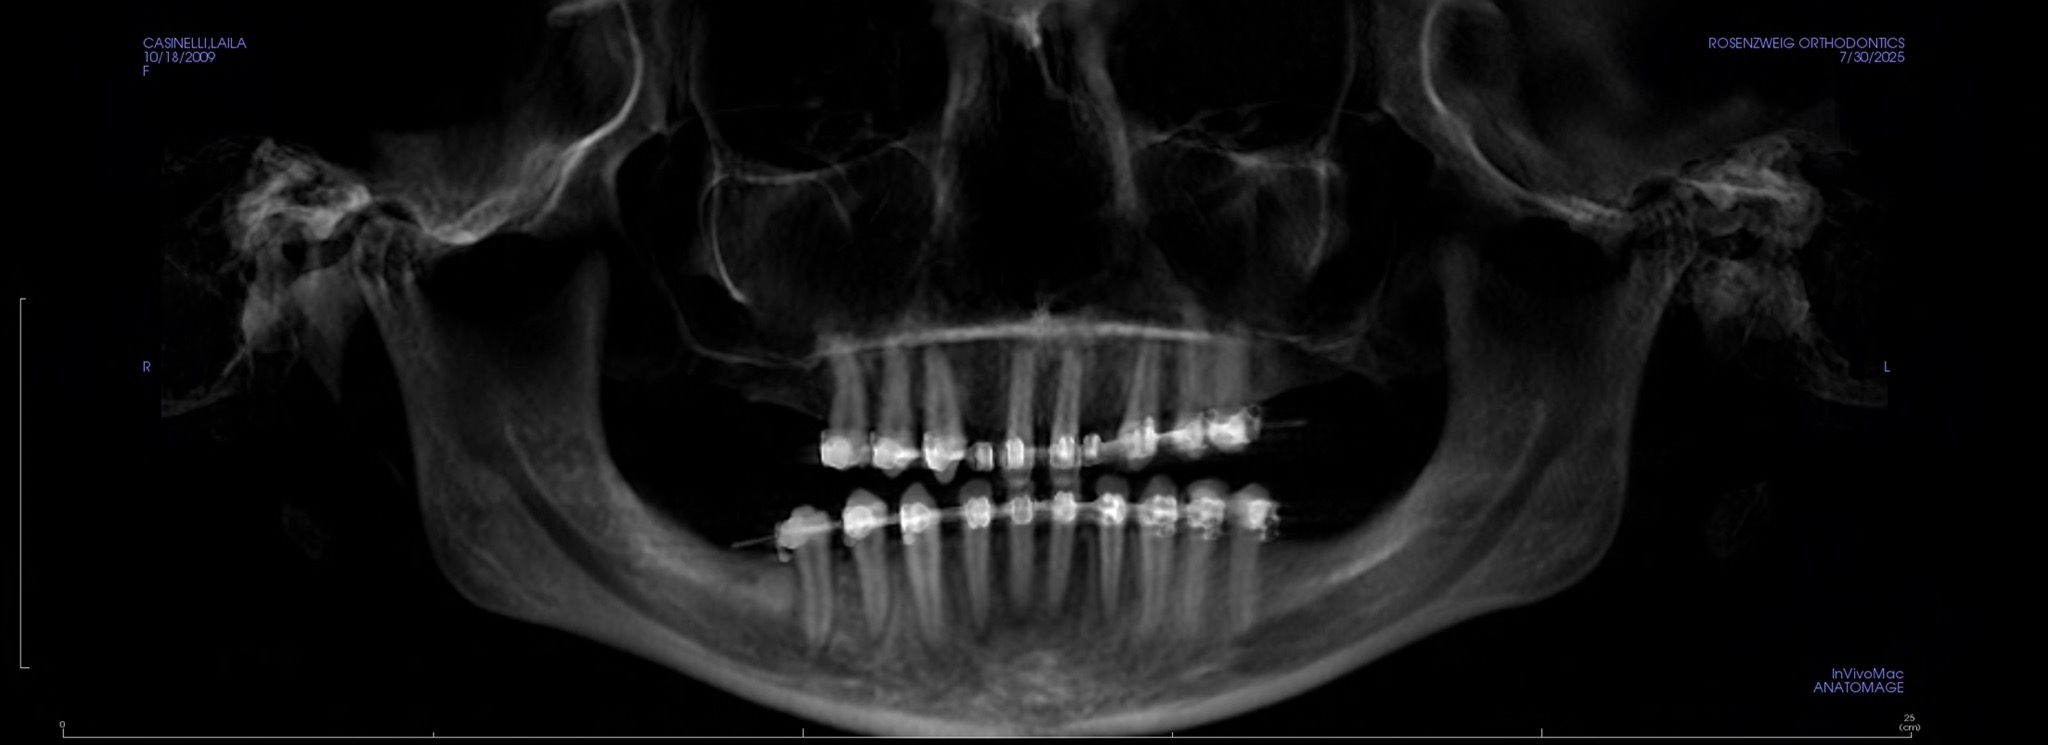

We were informed a few years ago that our daughter Laila is missing “14 permanent adult teeth” they just never came in. It is quite the anomaly and we are told by many specialists that she has a very unique situation and that this is not something that they have ever seen before or even see on a regular basis.

The diagnosis that they have so far given her is “Microdontia” a condition which the few teeth that did come in are abnormally small and not functional along with “Ogliodontia” being born without one or more permanent teeth (in her case 14 are missing). In conjunction with all the work that will need to be done to restore all of her teeth she will also be needing to undergo two extremely invasive surgical procedures, crown lengthening of the bone and enamel of her full mouth (removal of gums - scheduled in November 2025) and Mandibular advancement surgery a significant procedure where they will need to reconstruct her jaw due to certain abnormalities she was born with. There is also some speculation that she may possibly have a genetic disorder, called Pierre Robbin Sequence or Ehlos Danlos Syndrome and we are currently working with a Genetic Doctor to investigate all of this as well. The magnitude of all of this is daunting.

In 2023, we began the process once again and started interviewing and consulting specialists to try to build the best possible team and best course of action for our daughter. Knowing that it was going to be a huge mountain to climb and a lot to tackle yet we truly had no idea that the magnitude of this was going to be so immense. Because her situation is is so rare we hadn’t been well informed until now what the “FINAL”treatment plan was going to look like. The specialists here in Bend who are handling our situation have also been presenting Laila’s case to the Kois Institute in Seattle (one of the most advanced dental schools in the country) to further discuss how to handle the complexity of this medically fragile and unique situation.

Nevertheless we have been navigating the beginning stages (PHASE 1) of what’s going to be many, many years of reconstruction and restoration of Laila’s mouth, jaw and teeth. The timeline was on a stand still for a while because they were waiting for her skull to fully develop so we are now at the point of being able to move forward. It is unfortunate to have to do all of this during her formative High School years but we just don’t have much of a choice and don’t want to prolong it as she has already been feeling the effects of not having a “normal” smile or a “functional” mouth to be able to chew food etc.

- Orthodontic tooth movement to create adequate space - past 2 years ($6500 PAID)